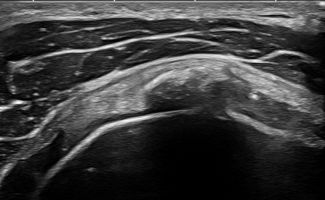

Με το Υπερηχογράφημα Ώμου μπορεί να εντοπιστεί συλλογή υγρού στα εξής σημεία:

- Υπακρωμιο-υποδελτοειδικός θύλακος

- Yποκορακοειδής θύλακος

- Γληνοβραχιόνιος άρθρωση